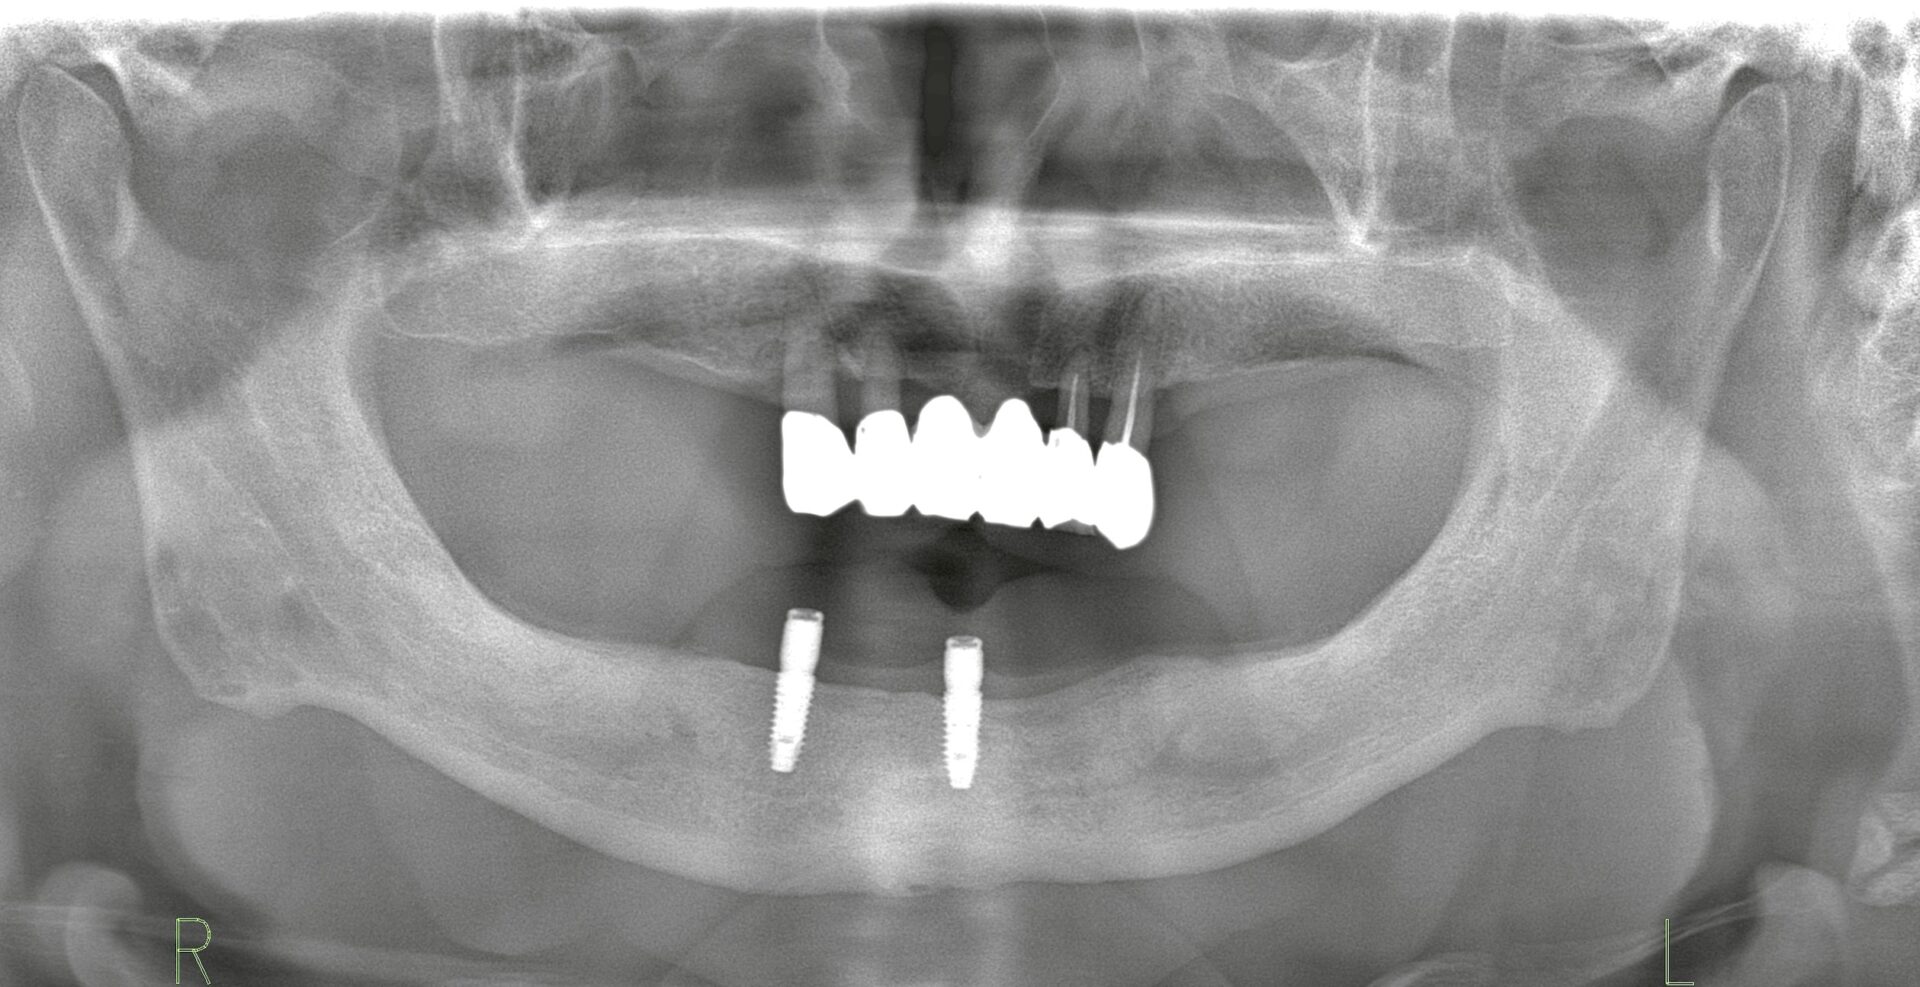

これらの薬は骨折予防やがんの骨転移抑制に大きな効果がありますが、歯科治療(特に抜歯やインプラント治療)で注意が必要な副作用=MROJ(薬剤関連顎骨壊死)が問題となることがあります。

BP製剤やデノスマブを使用中の方は、外科的処置によりMROJを起こす可能性があるため、治療計画を十分に立てる必要があります。

* 「骨粗鬆症だからインプラント治療は絶対に無理」というのも誤解で、慎重に診断・計画すれば治療できるケースもあります。